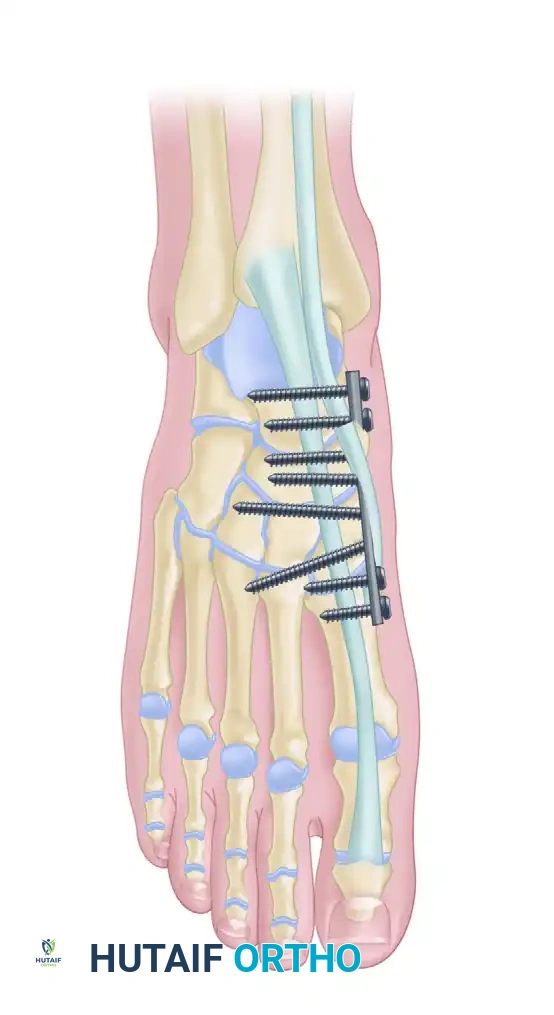

Operative Technique (ORIF):

1. Incisions: A dual dorsal incision technique is standard.

* Medial Incision: Centered over the first intermetatarsal space, lateral to the EHL tendon. This exposes the 1st and 2nd TMT joints. Protect the deep peroneal nerve and dorsalis pedis artery.

* Lateral Incision: Centered over the third intermetatarsal space to access the 3rd, 4th, and 5th TMT joints.

2. Reduction Sequence: Reduction must proceed from medial to lateral. The 1st TMT joint is reduced and provisionally pinned. Next, the critical 2nd TMT joint is reduced.

3. Fixation:

* The "Home Run Screw": A 3.5-mm or 4.0-mm solid cortical screw is placed from the medial cuneiform into the base of the second metatarsal, replicating the vector of the Lisfranc ligament.

* The 1st, 2nd, and 3rd TMT joints are typically rigidly fixed with transarticular screws or dorsal bridge plates.

* The 4th and 5th TMT joints are highly mobile. If unstable, they should be fixed with smooth Kirschner wires (K-wires) rather than rigid screws to preserve their essential sagittal plane motion. K-wires are typically removed at 6 weeks.